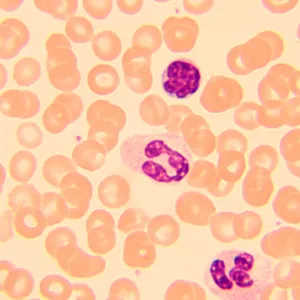

Биологический микроскоп MAGUS Bio 250B – оптический инструмент для изучения тонких прозрачных и полупрозрачных объектов. Основной метод исследований – светлое поле в проходящем свете. Микроскоп можно оснастить дополнительными аксессуарами для использования методов темного поля, фазового контраста и поляризованного света. Высококачественная оптика с дополнительными опциями, расширяющими ее возможности, удобная механика и продуманная конструкция делают этот микроскоп отличным выбором для лабораторной работы, научных исследований и обучения студентов.

Большой выбор аксессуаров позволяет настроить возможности MAGUS Bio 250B наиболее удобным для пользователя образом. Доступны окуляры, объективы, устройства для работы по методам темного поля, фазового контраста и поляризованного света, калибровочные слайды, цифровые камеры.